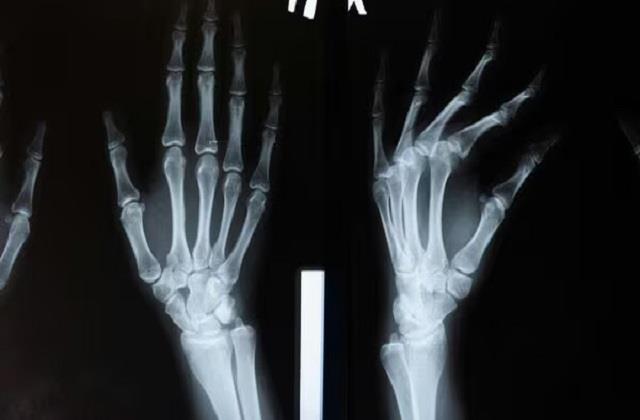

नारी डेस्क: इंसान शरीर मजबूत हड्डियों के सहारे खड़ा रहता है, अगर किसी की एक भी हड्डी टूट जाए तो वह लाचार जैसा महसूस करने लगता है । हड्डी टूटना कोई छोटी बात नहीं है इसे ठीक होने में हफ्तों या महीनों का समय लगता है। वैज्ञानिकों ने हाल ही में एक ऐसा ‘बोन ग्लू’ (Bone Glue) विकसित करने पर काम शुरू किया है, जो हड्डियों के फ्रैक्चर को कुछ ही मिनटों में जोड़ सकता है। यह शोध हड्डी के इलाज के क्षेत्र में क्रांतिकारी बदलाव ला सकता है।

चीन के एक ऑर्थोपेडिक सर्जन और उनकी टीम ने बोन-02 नामक एक गोंद विकसित किया है, जो सीपों की गीली सतहों पर चिपकने की प्राकृतिक क्षमता से प्रेरित है। सीप खुरदरी, पानी से भरी परिस्थितियों में भी चिपक जाते हैं, और इसी विचार ने शोधकर्ताओं को एक ऐसा गोंद तैयार करने में मदद की जो रक्त से भरपूर शल्य चिकित्सा क्षेत्र में भी टूटी हड्डियों को जोड़ सकता है। 150 से अधिक रोगियों पर परीक्षण किए गए, गोंद ने तनाव में भी मज़बूत जुड़ाव दिखाया, और केवल प्रयोगशाला परीक्षणों के बजाय वास्तविक सर्जरी में भी कारगर साबित हुआ।

यह गोंद जैसी परत बनाकर हड्डियों को मजबूती से जोड़ देता है। सामान्य तौर पर फ्रैक्चर को ठीक करने के लिए प्लास्टर, धातु की प्लेट, स्क्रू या रॉड का इस्तेमाल किया जाता है, जिसमें हफ्तों से महीनों का समय लगता है। लेकिन इस नए ‘बोन ग्लू’ से हड्डियां कुछ ही मिनटों में जुड़ सकती हैं और रोगी को लंबे समय तक प्लास्टर या बंधन की ज़रूरत नहीं होगी। एक केस के ट्रायल में तो यह पूरी प्रक्रिया 3 मिनट से भी कम वक्त में हो गई।